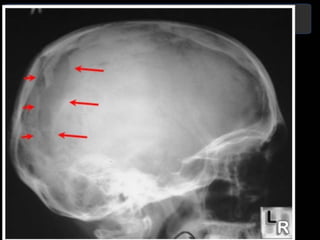

Radiología simple

1. De poca utilidad.

2. Proyecciones lateral,

anteroposterior y de Towne.

3. Existen fracturas que no son

visibles en la Rx simple.